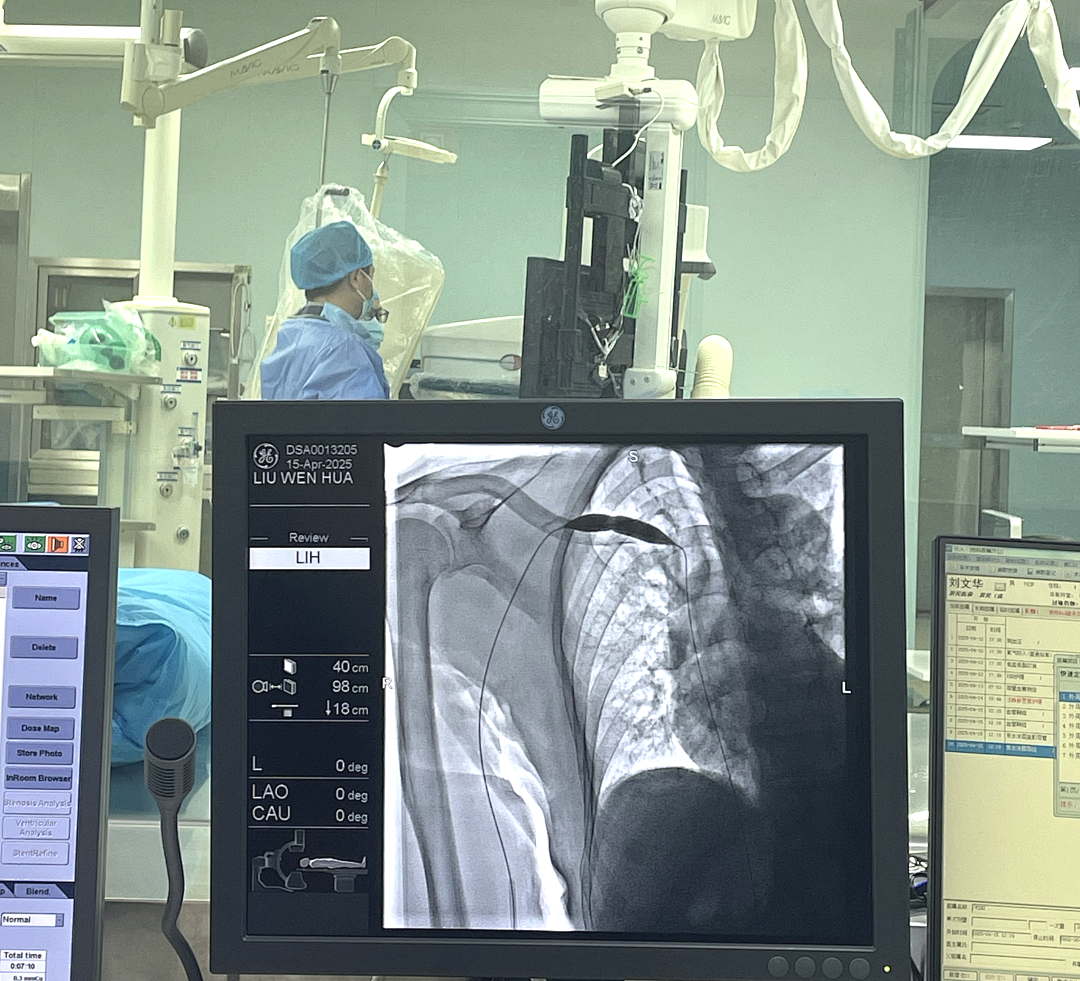

★超声/介入下球囊扩张术:针对内瘘狭窄,超声引导下精准扩张狭窄部位(无需开刀、恢复快);针对深部血管病变,借助DSA血管造影“导航”,清晰定位并处理复杂病变。

★介入下狭窄中心静脉扩张术:解决透析患者常见的“上游拥堵”——中心静脉狭窄,通过颈内/股静脉入路扩张狭窄血管,必要时放置支架,避免上肢肿胀与内瘘失功。